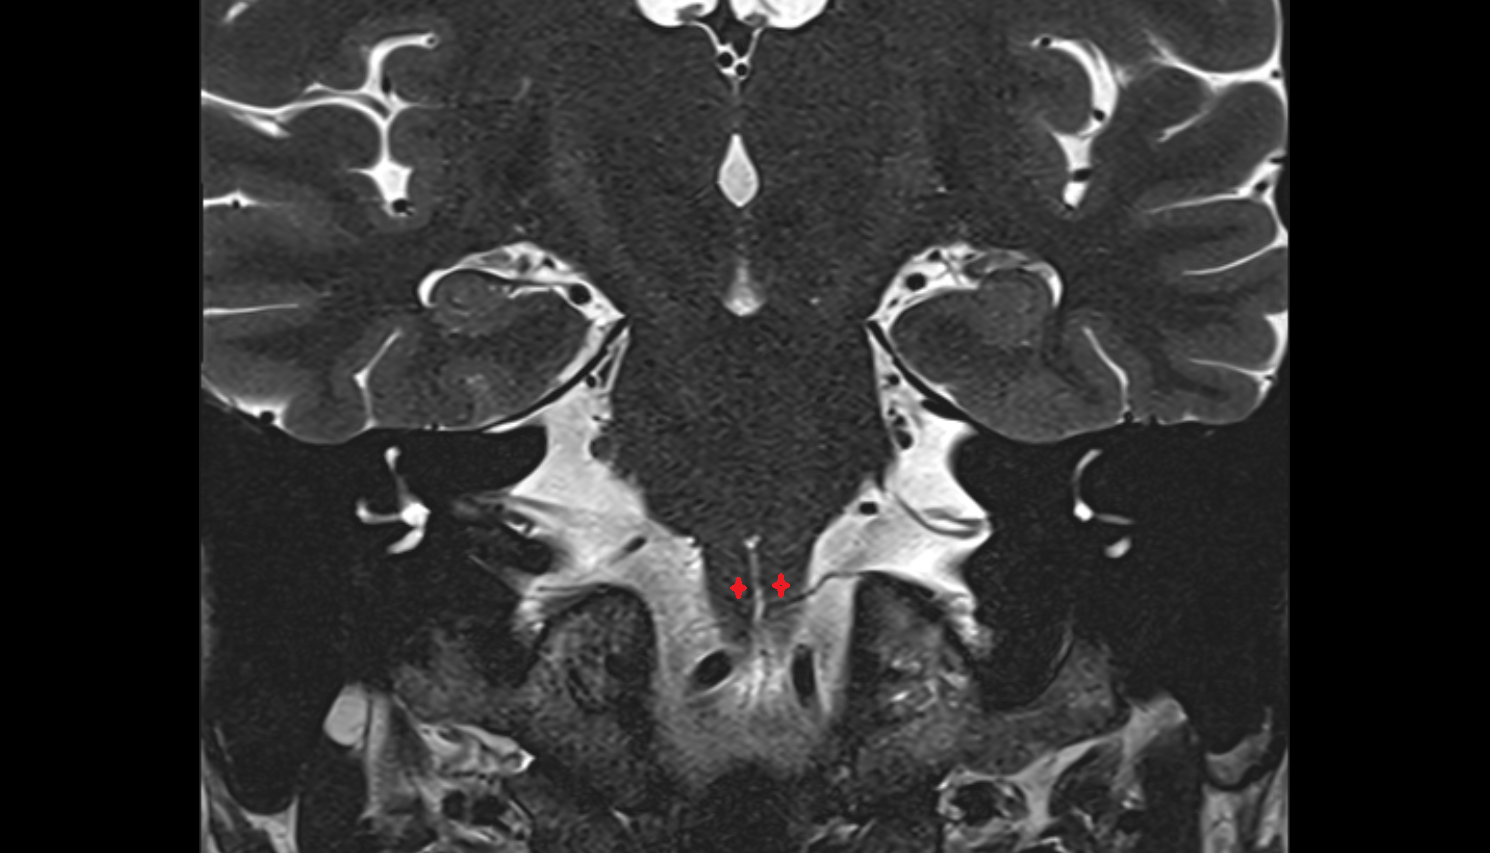

- Lateral aperture of fourth ventricle (foramen of Luschka)